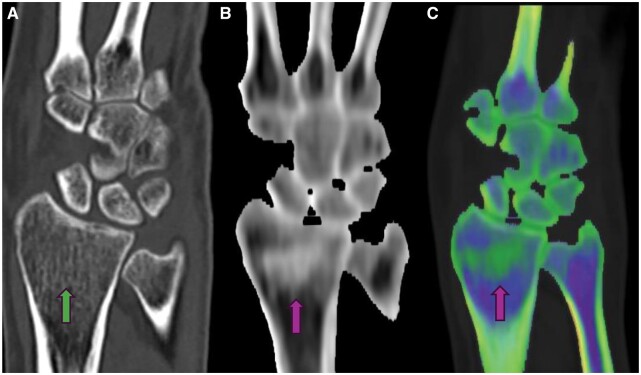

Dual-energy computed tomography (DECT) is an advanced imaging technique that acquires data using two distinct X-ray energy spectra, typically at 80 and 140 kVp, to differentiate materials based on their atomic number and electron density. This capability allows for the enhanced visualisation of various pathologies, including bone marrow oedema (BMO), by providing high-resolution images with notable energy spectral separation while maintaining radiation doses comparable to conventional CT. DECT's ability to create colour-coded virtual non-calcium (VNCa) images has proven particularly valuable in detecting traumatic bone marrow lesions (BMLs) and subtle fractures, offering a reliable alternative or complement to MRI. DECT has emerged as a significant tool in the detection and characterisation of bone marrow pathologies, especially in traumatic injuries. Its ability to generate high-resolution images and distinguish between different tissue types makes it a valuable asset in clinical diagnostics. With its comparable diagnostic accuracy to MRI and the added advantage of reduced examination time and increased availability, DECT represents a promising advancement in the imaging of BMO and related conditions.